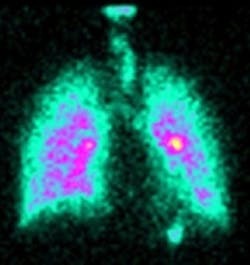

The diagnostic imaging technique combines the data from a gamma camera and CAT scanner, after which a 360º image of the lung is created. The technique allows the researchers to examine how a particular drug is inhaled, dispersed and exhaled from the lungs.

The image can then be used to inform experts on how best to optimize the administration and delivery of inhaled drugs such as antibiotics and anti-virals for diseases like asthma, but also future gene therapies for diseases such as cystic fibrosis.